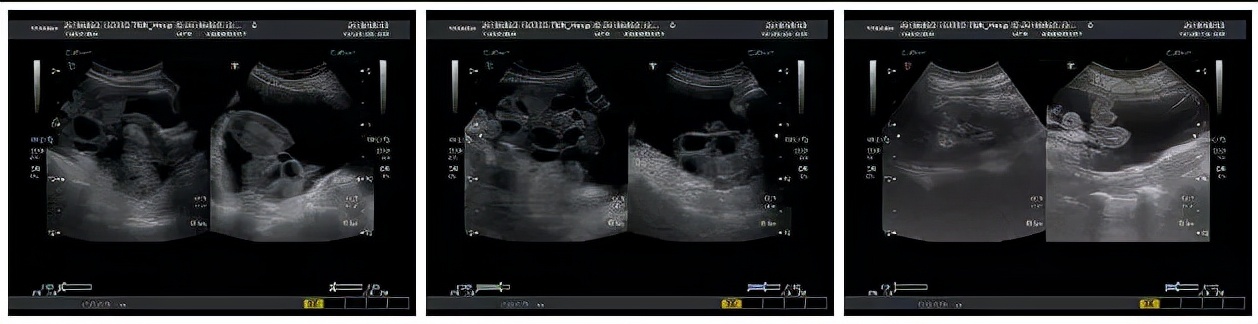

轻度 :表现为胃胀、食欲差、下腹不适、沉重感或轻微下腹痛。B超检查卵巢增大,直径≤5cm。

中度 :有明显下腹胀痛,可伴有恶心、呕吐、口渴,偶伴腹泻,体重增加≥3kg。B超检查卵巢增大,直径在5~10cm,腹腔积液<1.5L。

重度 :腹腔积液明显增加,尿少、恶心、呕吐、腹胀,严重者无法进食,疲乏,出冷汗,甚至虚脱。大量腹腔积液使膈肌升高或有胸腔积液时呼吸困难,不能平卧。B超检查卵巢增大,体重增加>4.5kg。